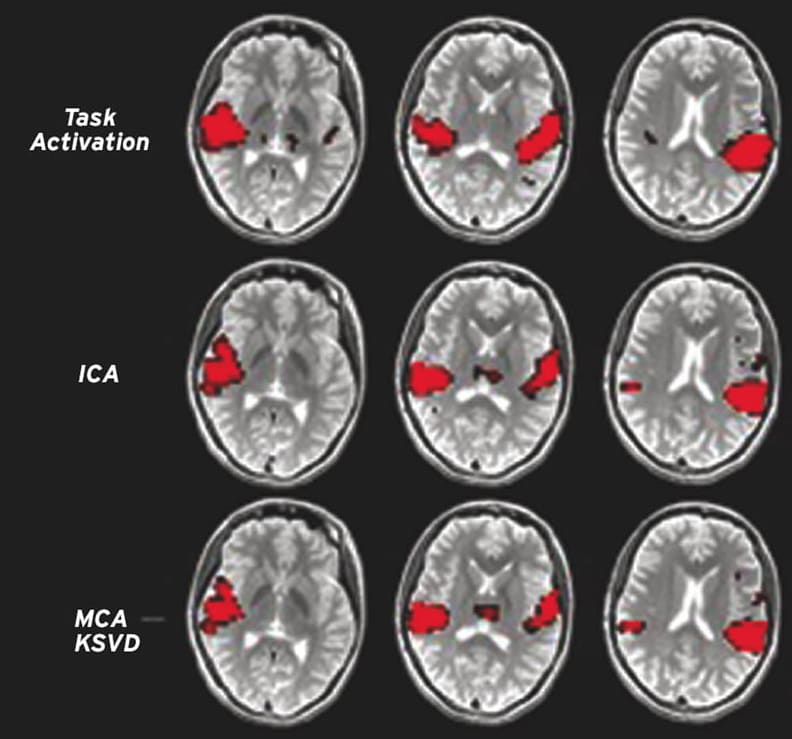

The report details the successful validation of the proposed methods through two case studies: one involving fMRI brain connectivity decomposition and the other focusing on breast cancer imaging. These case studies illustrated the effectiveness of the compressed sensing approach in achieving high-resolution images with reduced data input, thereby enhancing the efficiency of imaging processes.

Effects and capabilities of the method are further investigated and evaluated by applying it to the functional Magnetic Resonance Imaging (fMRI) and Dynamic Contrast-Enhanced (DCE-MRI) breast imaging as case studies. The project performs extensive analysis and evaluation of the proposed imaging method on the existing experimental data acquired by Prof. Dr. Gary H. Glover at Stanford University, Lucas center for MR imaging, Radiological Sciences laboratory, approved by the Stanford ethics review board. In addition, the project demonstrates the applicability of the proposed method in different imaging modality applications such as dynamic contrast-enhanced breast imaging, through the international research collaboration between PI and Dr. Wei Huang, Oregon Health and Science University, Advanced Imaging Research Center.